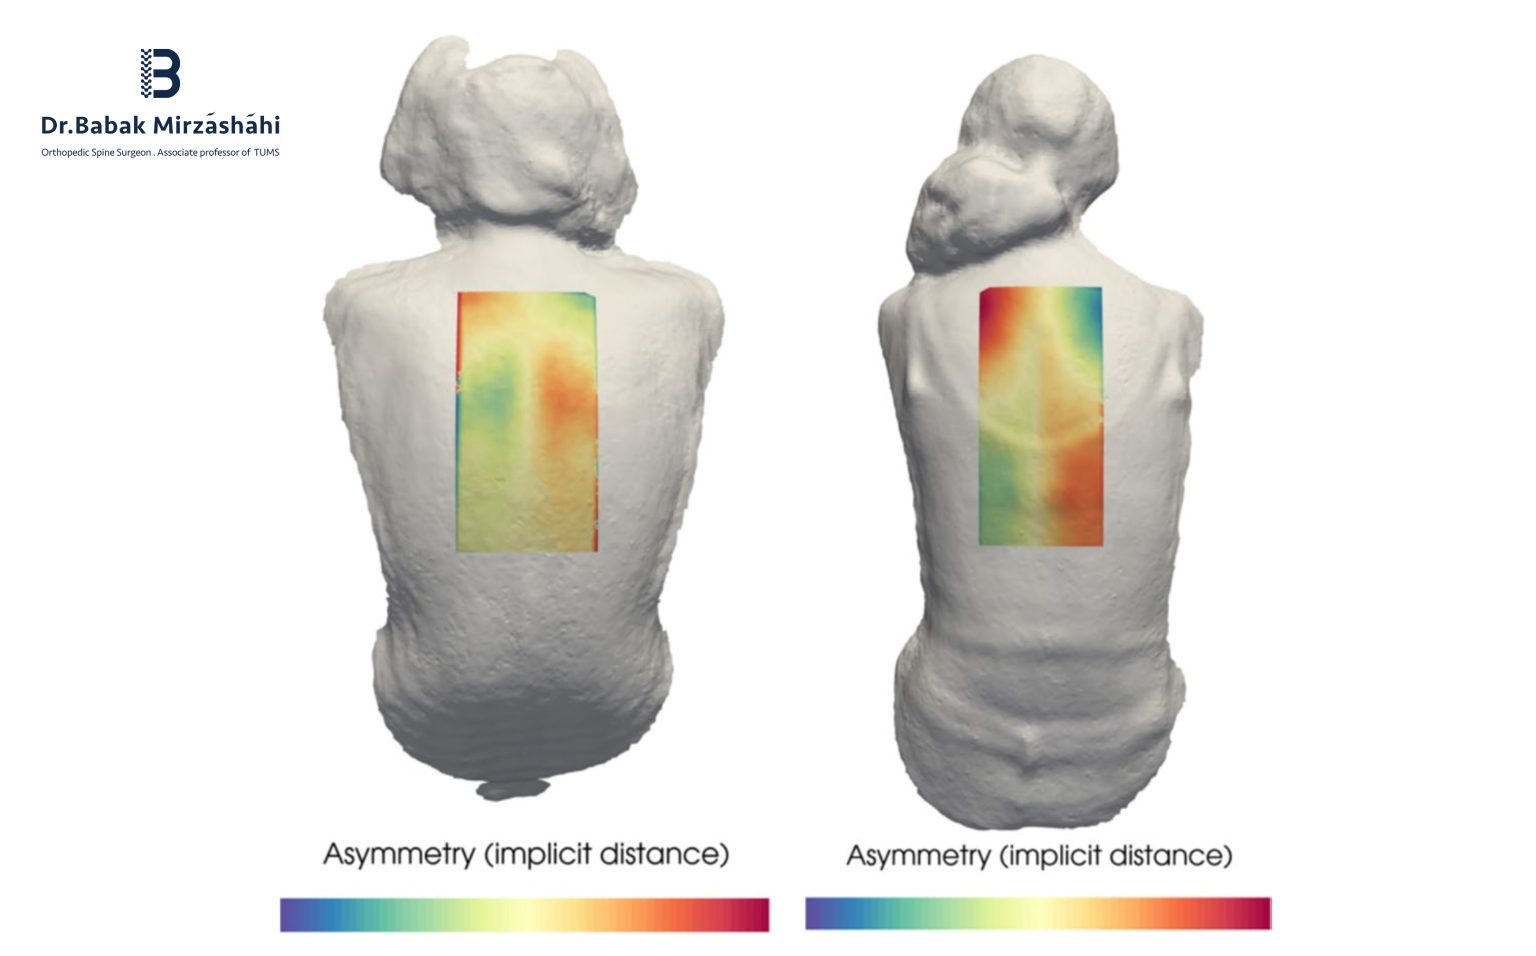

مدیریت درد، کنترل خونریزی و بهینهسازی تغذیه در جراحی اصلاح انحراف و ناهنجاری ستون فقرات مقدمه جراحیهای اصلاح انحراف ستون فقرات مانند اسکولیوز، کیفوز ... ادامه مطلب